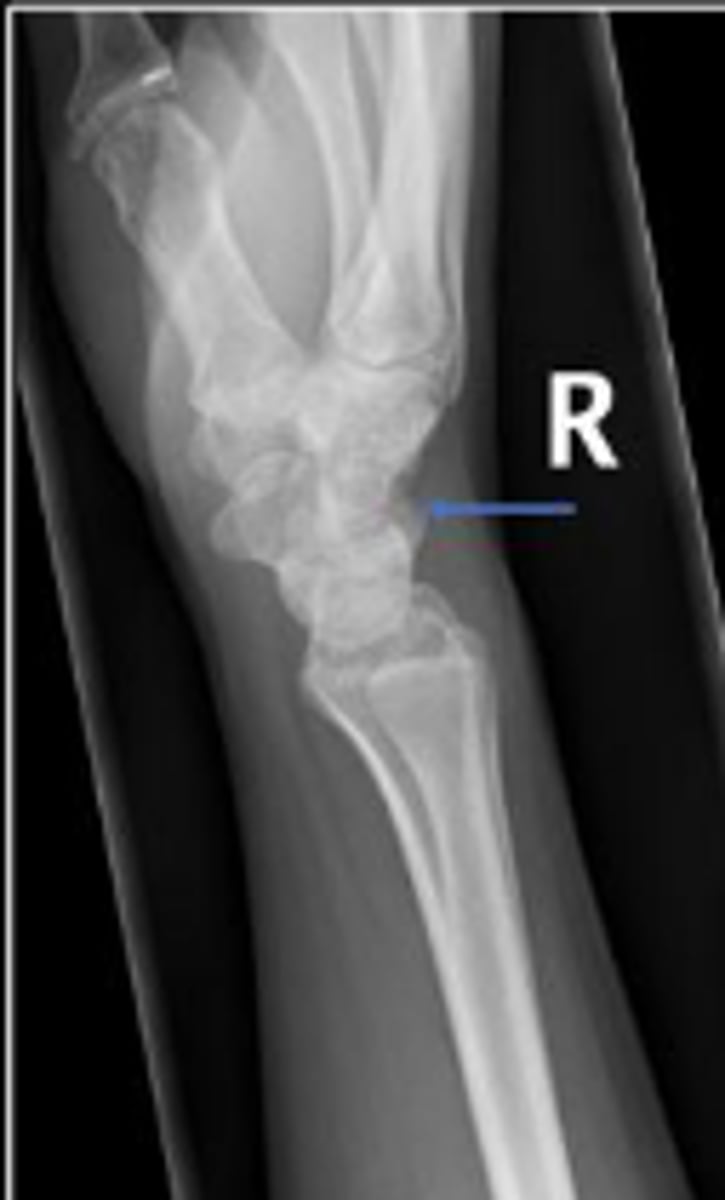

Left lateral wrist

What is the name of the radiographic view?

DRUJ

What is the arrow pointing to?

< and equal to 2mm

What is the normal measurement of this space?